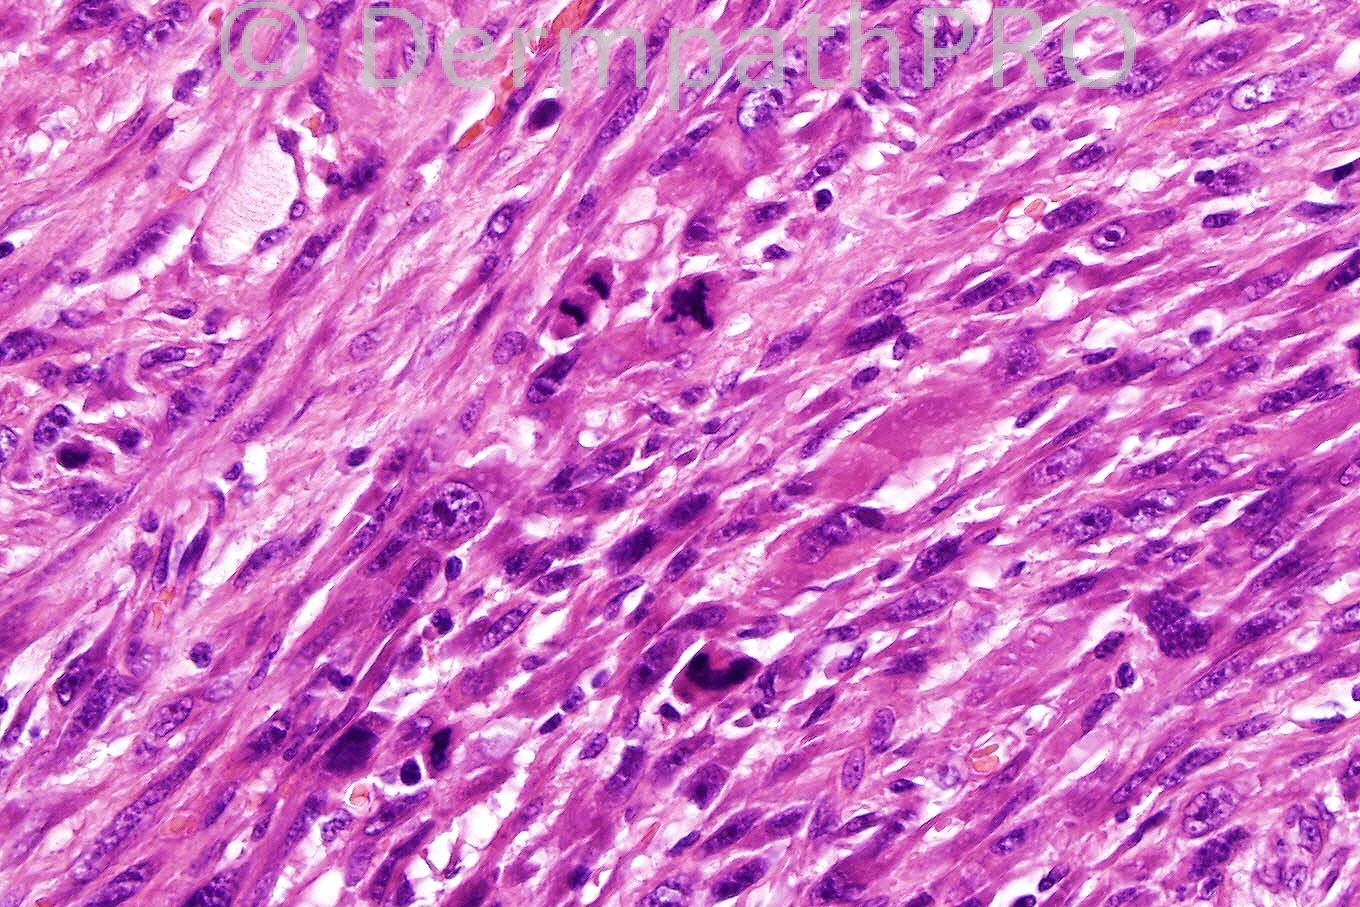

Female 92 years, lesion right cheek.

Najla asks (in case 502) how we should classify this tumour if it has an infiltrative pattern, but only superficial infiltration of the subcutis. My view is that it should be labelled cutaneous sarcoma NOS and a comment made that there may be a small risk for metastasis (if infiltration is only superficial). Eduardo Calonje, Thomas Brenn and colleagues have collected a series of deeply invasive "cutaneous pleomorphic sarcomas" with a metastatic rate of 10% (recent up-date lecture). I think the bottom line is the more infiltrative the tumour and the deeper extent of subcutaneous invasion the greater probability for metastatic potential (not to mention vascular invasion). We have collected a small number of cases (unpublised) of otherwise immunophentypically typical AFX confined to the dermis but with infiltrative ("superficial spreading") borders - how these should be classified I really don't know! Up till now AFX with pushing margins confined to the dermis or only superficial pushing subcutaneous involvement have not been reported to metastasise.

Well done again the was a case of AFX (immunostains must be performed - I usually limit my panel to CD10 diffuse in AFX and negative S100, pan-keratin and p63 for typical cases). Lesion must of course be circumscript with only superficial pushing subcutaneous involvement. DFSP does not usually present in this way and the tumour is far to pleomorphic in any case. Regards to all.

Favour AFX (atypical fibroxanthoma). DD: spindled SCC, desmoplastic MM. IHC: pancytokeratins, S100 protein, HMB45, CD68.